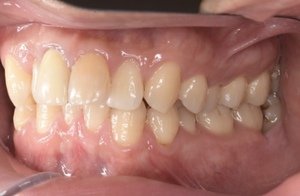

CASE 3

Before

After

基本情報

| 年齢・性別 | 30代・女性 |

|---|---|

| 主訴 | 定期検診 |

| 治療内容 | PMTC |

| 治療期間 | 60分 |

| 治療費 | 5,750円 |

| リスク・副作用 | しみる可能性があります。 |

| 治療方針 | PMTCでステインの除去。 |

| 担当者所見 | ステインが付きやすいため、3カ月毎の定期検診で除去する。 |